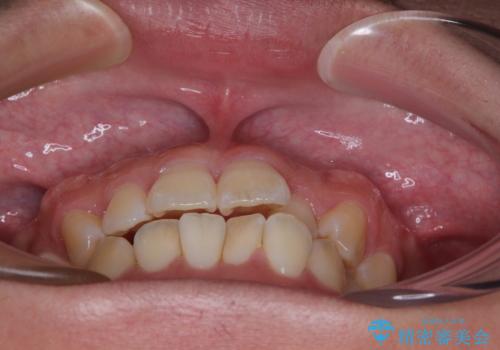

- 前歯の反対咬合などを気にして来院された患者様です。

ワイヤー矯正、マウスピース矯正どちらでも対応可能であったので、ご本人の希望によりインビザラインにて矯正治療を行うこととしました。

マウスピース矯正は、ワイヤー矯正と違い、とにかく自己管理が非常に重要となります。

毎日の装着時間をしっかりと守ってくださり、1年強の短期間で、あっという間に治療を終えることができました。